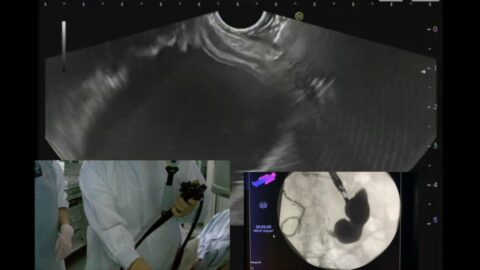

Mise en place d’une prothèse de sauvetage par écho-endoscopie après migration de prothèse d’hépatico-gastrostomie en intra-péritonéal